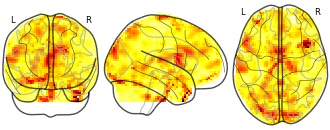

"name": "Multi_VBMsmaller_fMRIenhanced",

"description": "Multi-modal analysis in BPD. Brain regions exhibiting smaller gray matter and enhanced activation during emotion processing in BPD compared to healthy controls. Note: Results were thresholded at p<.0025. Note2: Results were updated (see Erratum for this publication).",